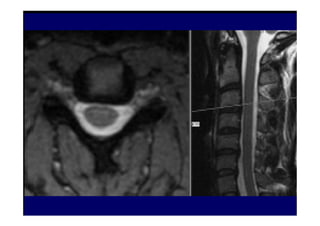

• 3. Ressonância Magnética

Opção preferencial para detecção de

patologias de partes moles tais como hérnia

de disco e tumores. Estudo realizado em 100

pacientes com doenças na laringe, sem

queixas clínicas relacionados à coluna cervical,

evidenciaram 20% de lesão discal em

pacientes entre 45-54 anos e 57% com mais de

64 anos.

07/12/2015 Dr. José Heitor M. Fernandes 76Neuroimagem

figura

07/12/2015 Dr. José Heitor M. Fernandes 77